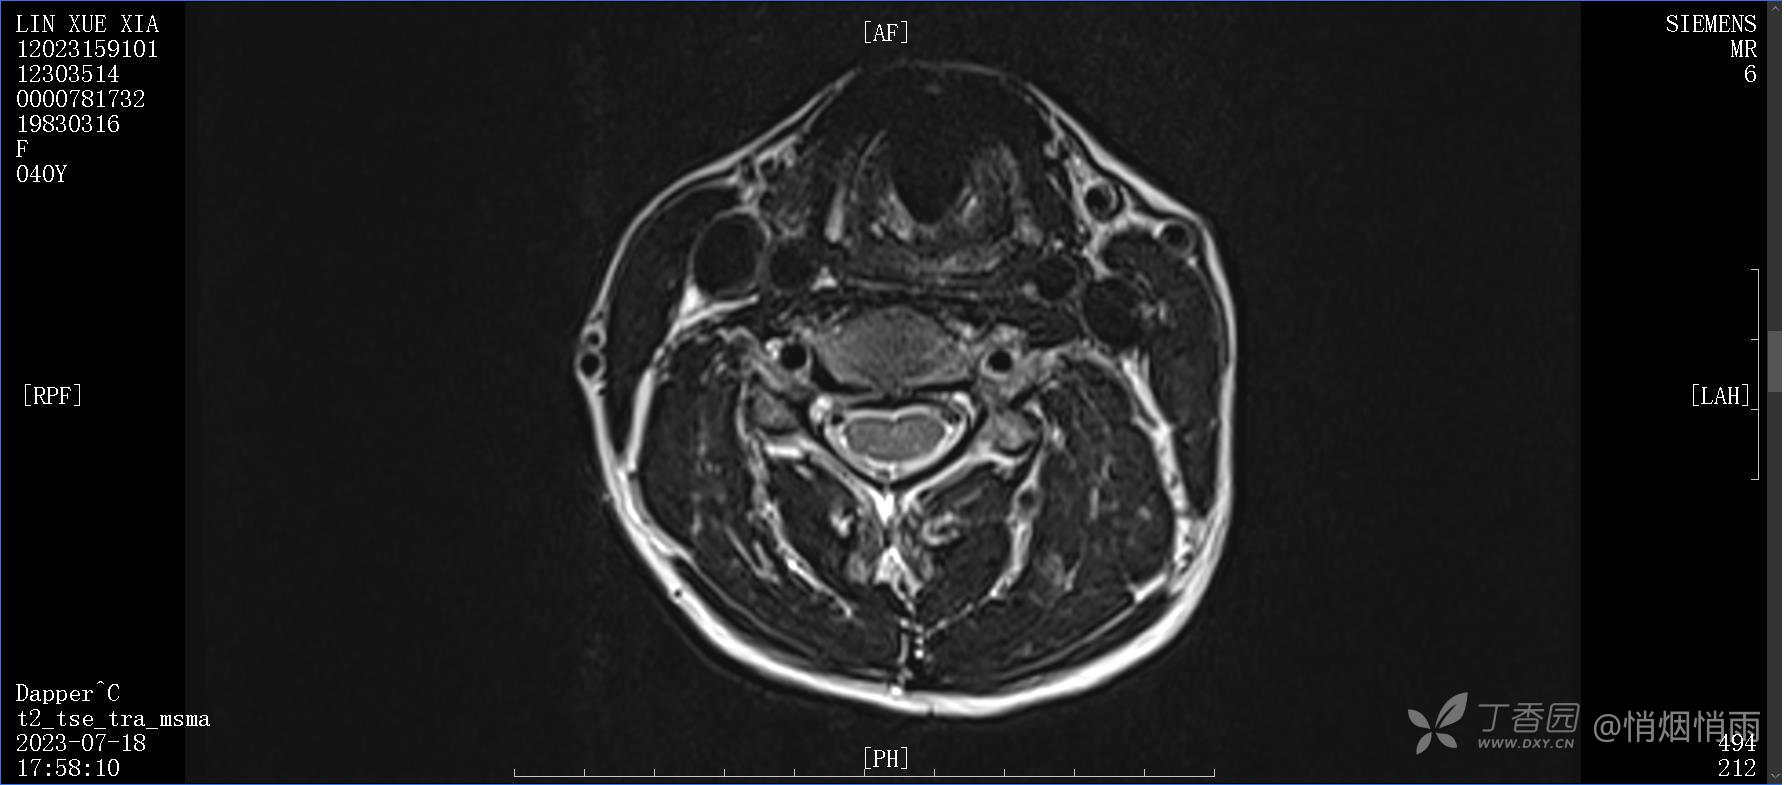

辅助检查:

目前的诊断,暂时依据辅助检查诊为肩袖损伤,但是患者疼痛的性质和特点,却不是单纯的肩袖损伤所致。考虑过胸廓出口综合征,但是该疾病会出现肩胛区的疼痛吗?(由于考虑到费用的问题,没再进行下一步的检查)带状疱疹会有如此的症状吗?